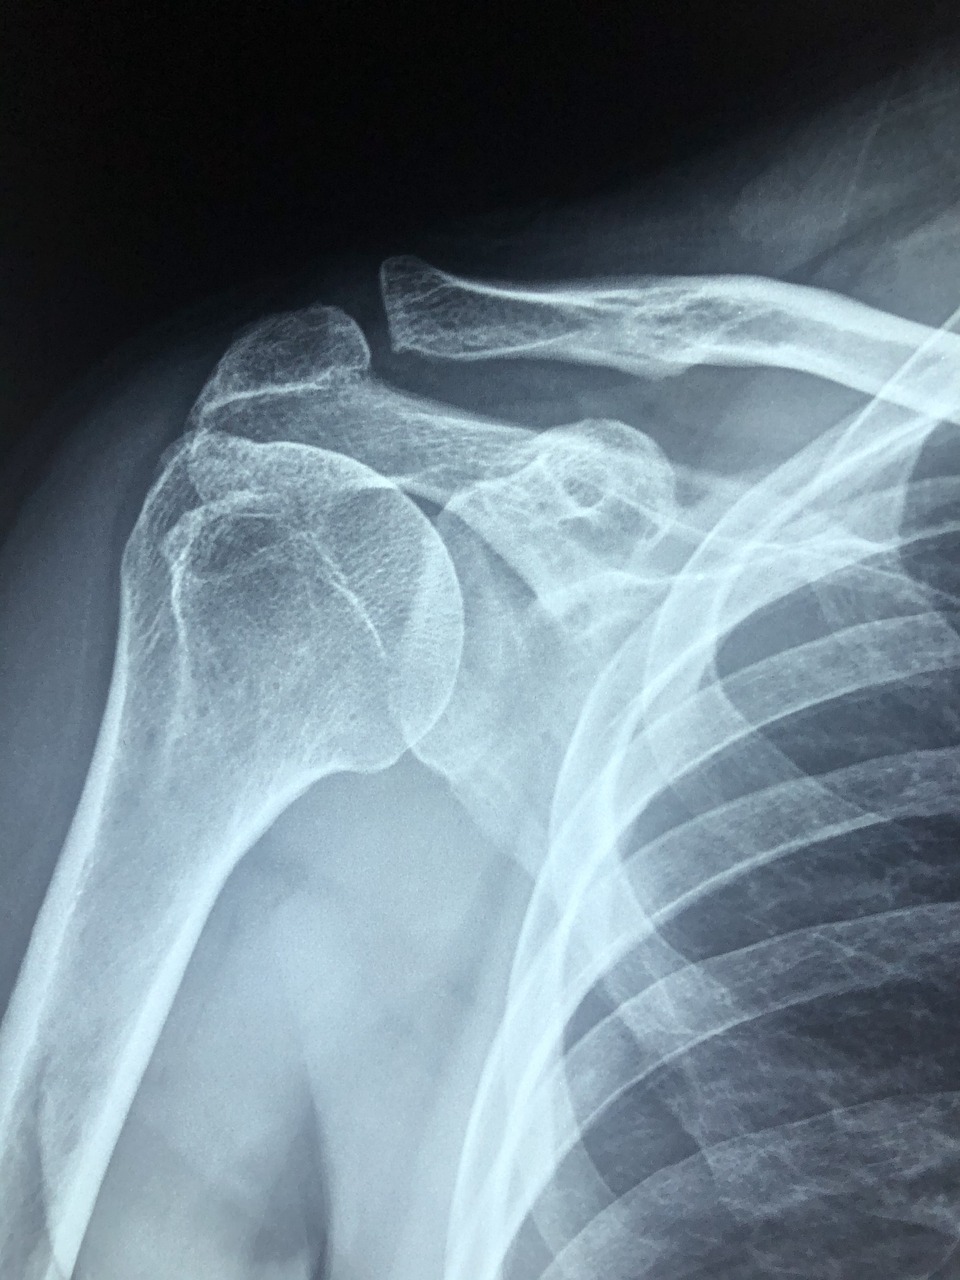

통증이 심하거나 일상생활에 불편을 줄 정도라면 흉부 X-ray 검사를 통해 골절 여부를 확인하고, 필요시 코르셋이나 흉대 착용으로 통증을 경감시킬 수 있습니다.